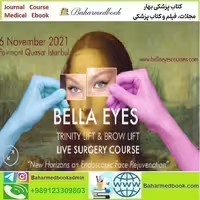

Bella Eyes Trinity Lift & Brow Lift Live Surgery Course 2021 video

700,000 تومانء

در کتاب پزشکی بهار